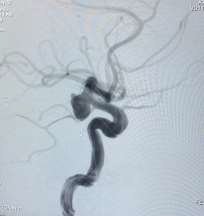

Observe a angiografia abaixo:

Imagem cedida pelo autor

De acordo com o achado nessa angiografia, assinale a alternativa CORRETA.